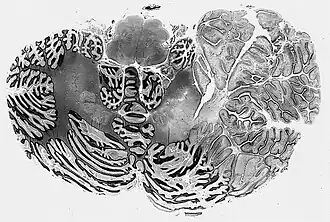

![]() Corte de cerebelo mostrando un gangliocitoma displásico. | ||

La enfermedad de Lhermitte-Duclos (gangliocitoma displásico cerebeloso, LDD) es una enfermedad rara consistente en un crecimiento lento de un tumor en el cerebelo, a veces considerado un hamartoma, caracterizado por una hipertrofia difusa del estrato granuloso del cerebelo. A menudo suele asociarse con síndrome de Cowden y es patognomónico para esta enfermedad.[1] Fue descrita por Jacques Jean Lhermitte y P. Duclos en 1920.[2]